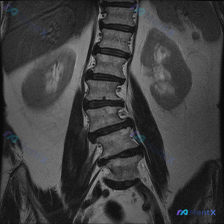

看到一张腰椎MRI冠状位,提示轻度左侧凸侧弯,你会先考虑良性退变还是其他?

网上看到一份腰椎MRI T2序列冠状位的影像资料,先抛出来和大家讨论一下读片思路。

影像里看到的主要信息整理了一下:

- 脊柱序列:腰椎生理曲度轻度侧弯,凸向左侧,各椎体排列基本连续,没看到明显滑脱错位

- 椎体与骨髓:各腰椎椎体形态大致规则,边缘有轻度骨质增生;骨髓T2信号均匀高信号,没看到明显异常低信号灶或溶骨性破坏

- 椎间盘与椎间隙:椎间隙高度基本还行,椎间盘T2信号不均匀减低,有“黑盘”表现;冠状位没看到明显的椎间盘侧向突出压迫神经根(但报告提了要结合轴位)

- 椎管、软组织、邻近器官:腰椎椎管形态大致对称,两侧腰大肌、竖脊肌信号对称,双侧肾脏也没看到明显异常肿块

这份资料的核心焦点是「脊柱侧弯」的性质——